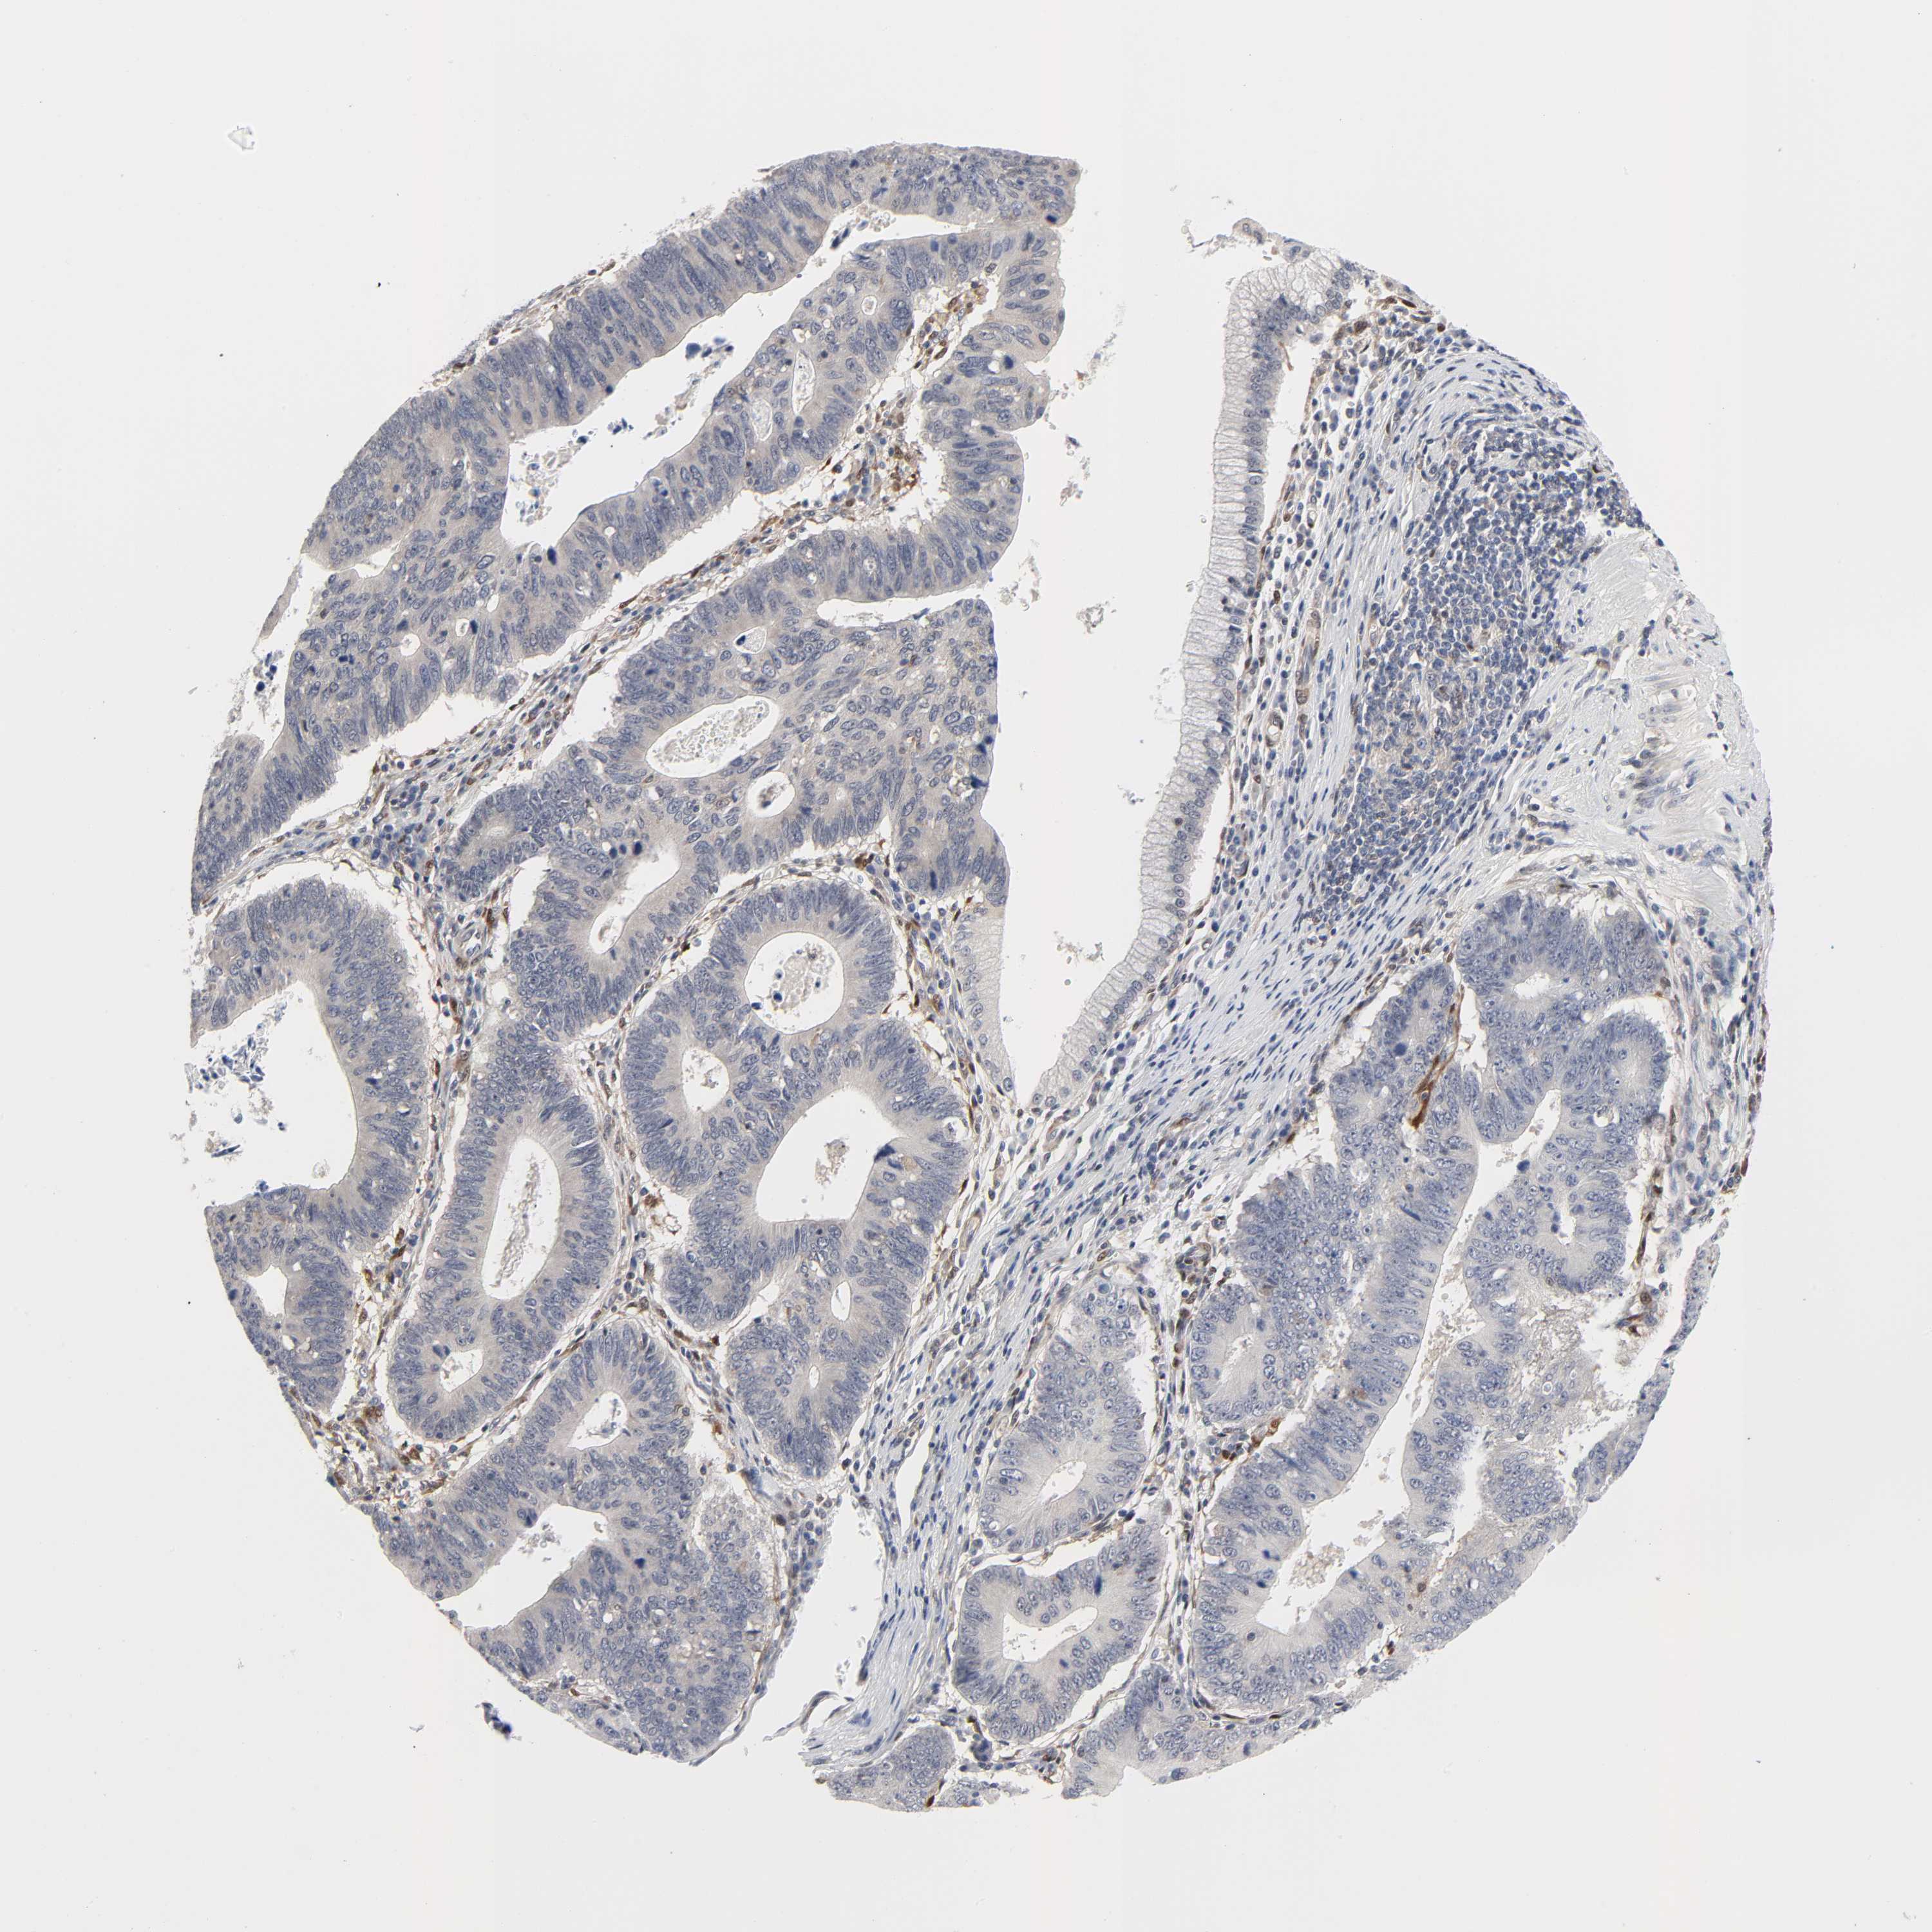

STOMACH CANCER - Protein expressioni

A mouse-over function shows sample information and annotation data. Click on an image to view it in a full screen mode. Samples can be filtered based on level of antibody staining by selecting one or several of the following categories: high, medium, low and not detected. The assay and annotation is described here.

Note that samples used for immunohistochemistry by the Human Protein Atlas do not correspond to samples in the TCGA dataset.

Antibody stainingi

Antibody staining in the annotated cell types in the current human tissue is reported as not detected, low, medium, or high, based on conventional immunohistochemistry profiling in selected tissues. This score is based on the combination of the staining intensity and fraction of stained cells.

Each image is clickable and will lead to virtual microscopy that enables deeper exploration of all samples and also displays staining intensity scores, fraction scores and subcellular localization as well as patient and tissue information for each sample.

Antibody HPA031335

Antibody CAB004076

Antibody CAB080153

Antibody CAB080157

Staining

High

Medium

Low

Not detected

Intensity

Strong

Moderate

Weak

Negative

Quantity

>75%

75%-25%

<25%

None

Location

Nuclear

Cytoplasmic/membranous

Cytoplasmic/membranous,nuclear

Adenocarcinoma, NOS

Adenocarcinoma, High grade